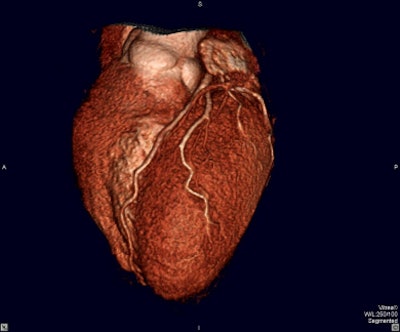

Taking data from cross-sectional CT and MRI studies, 3D technology creates spatial views of organs and systems, allowing physicians to visualize a patient’s anatomy realistically. Multiplanar reconstruction (MPR) review is now becoming the standard of care for interpretation of multidetector CT (MDCT) studies.

MPR gives an oblique plane through a volumetric dataset that the radiologist can control arbitrarily to view structures out of the plane of the original 2D slice images acquired by the scanner. In addition to more-accurate diagnosis, 3D enables noninvasive surgical planning, resulting in reduced operating time and less damage to healthy tissue when the target area is isolated.

In neurosurgery, 3D visualization of cerebral vasculature from CT angiography aids surgical planning for aneurysms, allowing surgeons to spare crucial cortical areas and reducing operating time.

Vascular surgeons use 3D angiography and multiplanar views to design aortic stents.

Radiologists often say they can make a diagnosis on an axial 2D image, but MPR is becoming the standard of care. And the challenge is even greater for surgeons. Unlike the radiologist, the surgeon must sit down with his or her patient and explain what he or she proposes to do in the operating room. The surgeon has to convince the patient that the proposed procedure is best for him or her.

As Christoph Wald said, "You have no idea how powerful it is for surgeons to have one image that shows the aneurysm or the tumor, and say to the patient, ‘Look, here it is. This is what it looks like. This is what I need to get at.’ The traditional drawing surgeons make for patients has been replaced by powerful imagery. Surgeons love it.